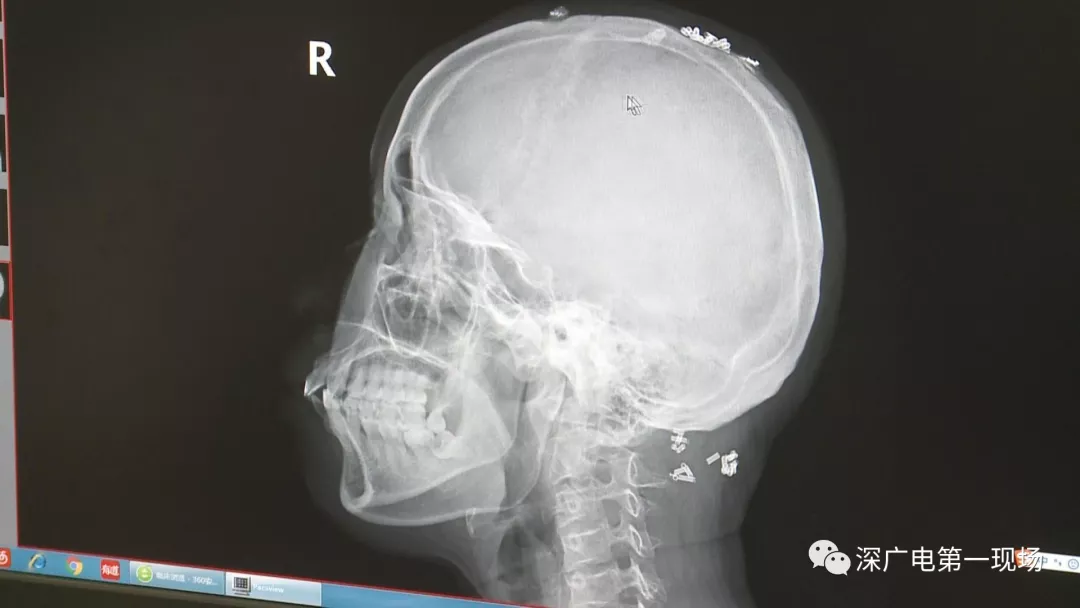

從X光影像圖片中可以看到

患者周身布滿(mǎn)了彈簧圈

深圳大學(xué)總醫(yī)院神經(jīng)外科副主任醫(yī)師陳富勇介紹,當(dāng)時(shí)檢查的時(shí)候發(fā)現(xiàn),該患者從頭部到腿部,基本上每個(gè)地方都有彈簧,很難數(shù)清具體數(shù)目。